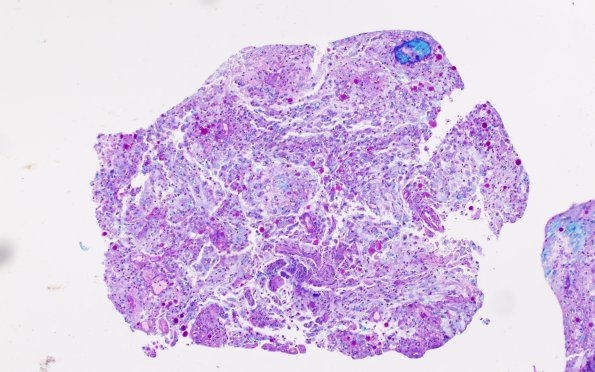

17C1 Demyelination, inflammatory (Case 17) LFB-PAS 10X 1

17C1,2 LFB-PAS shows total breakdown of normal myelin architecture. (LFB-PAS)